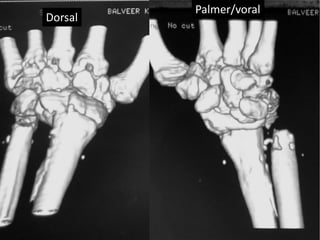

Severe Palmer flexion and ulnar deviation deformity

Dorsal

Palmer/voral

Ulnar Radial

Palmer surface